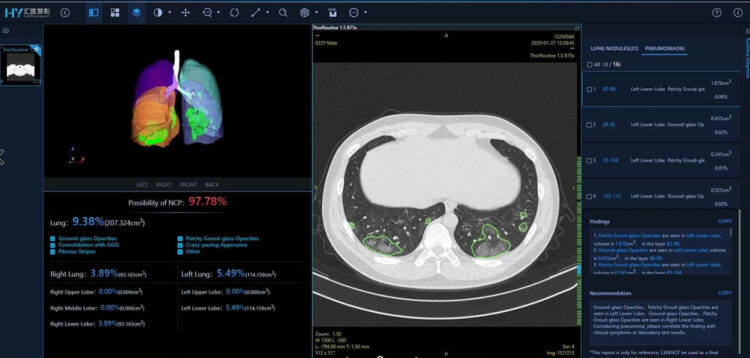

ส่วนในประเทศฟิลิปปินส์ โรงพยาบาลและศูนย์แพทย์บาเกียว (Baguio General Hospital and Medical Center) ได้ติดตั้งโซลูชันคัดกรองผลตรวจ CT ด้วยผู้ช่วย AI (AI-assisted CT Screening) ของหัวเว่ย เพื่อช่วยแพทย์ตรวจหาผู้ป่วยโควิด-19

โซลูชันผู้ช่วย AI เพื่อการวินิจฉัยโรคของหัวเว่ย ซึ่งตั้งอยู่บนแพลตฟอร์มของ HUAWEI CLOUD ช่วยลดระยะเวลาการวินิจฉัยโรค และทำให้สามารถระบุและยืนยันเคสผู้ป่วยที่สงสัยว่าติดเชื้อโควิด-19 ได้รวดเร็วขึ้น โดยระบุระยะของการติดเชื้อได้อย่างแม่นยำว่าอยู่ในระยะเริ่มต้น ระยะลุกลาม หรือระยะรุนแรง จึงประหยัดเวลาในการรักษา

ในด้านสาธารณสุข HUAWEI CLOUD มีแพลตฟอร์ม EIHealth ที่ประกอบด้วยบริการต่างๆ เช่น การตรวจหาจีโนมของไวรัส (viral genome) การทดสอบยาต่อต้านไวรัสด้วยกระบวนซิลิโคสกรีนนิ่ง (silico screening) และการคัดกรองผู้ป่วยโดยใช้ผู้ช่วย AI วิเคราะห์ผลตรวจ CT scan